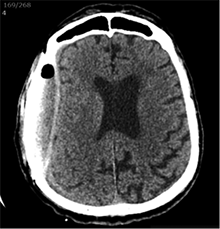

Po 2 savaičių pacientas rastas parkritęs kieme. Buvo matyti kraujuojanti žaizda. Pacientas pakartotinai hospitalizuotas į Neurochirurgijos skyrių. Atlikus GKT, nustatyta 25 mm storio hipodencinė juosta virš dešiniojo smegenų pusrutulio ir 8 mm vidurinių smegenų struktūrų dislokacija (VSD) į kairę (3 pav.). Įtariant lėtinę SDH dešinėje pusėje, pacientas reoperuotas, atliekant rekraniotomiją. Operacijos metu ant kietojo smegenų dangalo (KSD) rasta fibrino, jis pašalintas. Pravėrus KSD, rastas drumstas turinys, nesant aiškių pūlių, ir stora kapsulė. Gausiai praplauta šiltu fiziologiniu tirpalu subduraliai. Kaulinis lopas grąžintas (4 pav.). Po operacijos pacientas pradėjo skųstis stipriu galvos skausmu, tapo vangus. GKT pakartota. Įtarta empiema, nustatyti oro tarpai subduraliai, galvos smegenų VSD – 6 mm. Praėjus 12 dienų po antros operacijos, pacientas operuotas pakartotinai. Operacijos metu atlikta rekraniotomija. Epiduriniame ir subduriniame tarpuose rasta pūlių ir fibrino. Pūliai ir fibrinas pašalinti, paimtas bakteriologinis pasėlis. Žaizda gausiai praplauta šiltu fiziologiniu tirpalu. Kaulinis lopas negrąžintas, minkštieji audiniai susiūti (5 pav.). Po operacijos paciento būklė stabilizavosi. Bakteriologiniame pasėlyje negausiai užaugo E. coli, jautri ampicilinui. Nesant teigiamo efekto gydant ampicilinu, dar 2 savaites pacientui skirta gentamicino. Praėjus 3 savaitėms po trečios operacijos, pacientas perkeltas į slaugos ligoninę palaikomojo gydymo.

3 pav. Prieš antrąją operaciją (25 mm storio hipodencinė juosta virš dešiniojo smegenų pusrutulio, esant 8 mm dislokacijai į kairę; įtarta lėtinė SDH dešinėje)